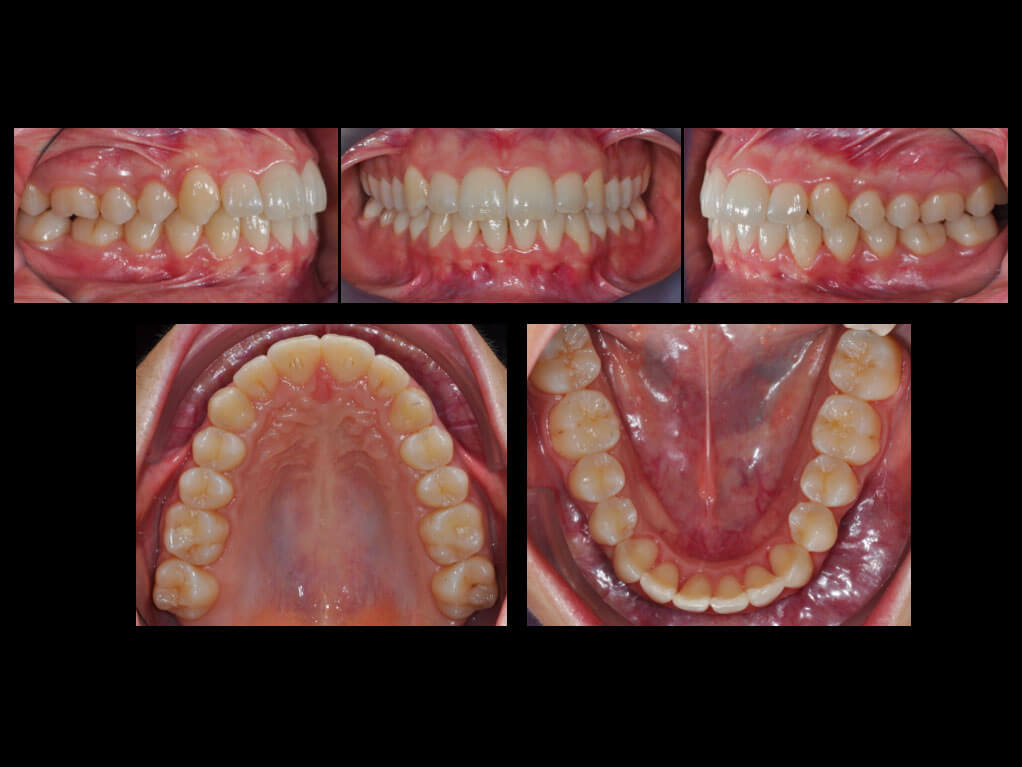

Treatment was completed in approximately eight months. The crowding in the lower arch was resolved, while a good Class I molar and canine relationship was consolidated. The incisor overbite and overjet relationships were maintained, and the upper and lower interdental midlines were centred.